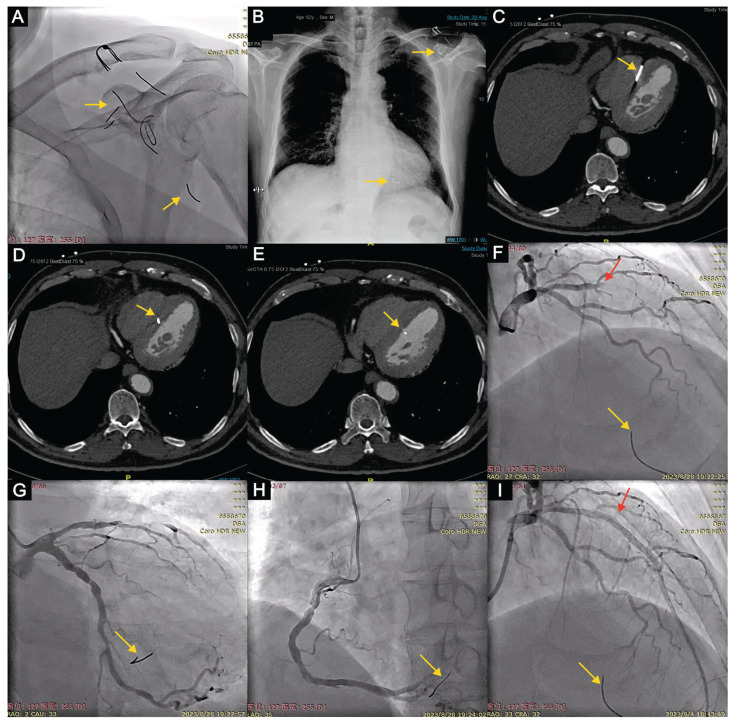

Fractured wire migrated from left clavicle into the heart.

断裂的金属丝从左锁骨进入心脏。